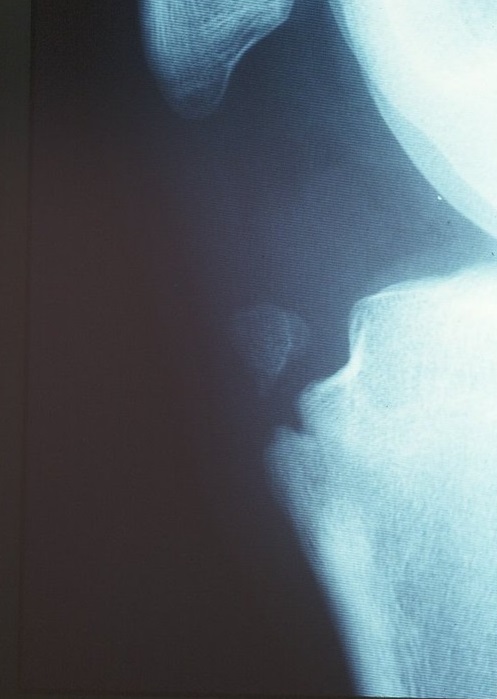

レントゲン検査が最も有用で、脛骨粗面に限局した骨端核の変化や遊離骨片を認めますが(写真2)、成長段階によって大きさは異なります。MRIはさらに有用で、骨軟骨を覆う膝蓋腱の肥厚や周囲の炎症性変化が確認できます(写真3)。超音波でも突出した骨や腱の肥厚、血管新生を確認できます。(写真4、5)

写真2 レントゲン